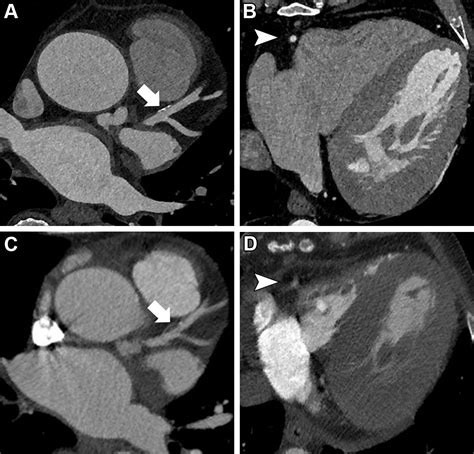

At its core, a Cardiac CT scan is an imaging test that allows cardiologists and radiologists to see if your coronary arteries are narrowed or blocked by plaque buildup—a condition known as atherosclerosis. Unlike traditional stress tests, which provide functional information about how your heart handles exertion, a cardiac CT provides anatomical information. It captures images of the heart while it is beating, using sophisticated gating technology to synchronize the image acquisition with your heart rhythm.

This technology is particularly effective at identifying early-stage heart disease before symptoms manifest. By visualizing the calcified and non-calcified plaque within the arterial walls, physicians can initiate preventative treatments far earlier than previously possible.

Once the scan is complete, the images are sent to a radiologist or a specialized cardiologist who analyzes the anatomy of your coronary arteries. They will look for the presence and extent of plaque, the degree of arterial narrowing (stenosis), and the presence of any calcium deposits. You will receive a formal report, and your primary doctor will discuss the findings with you to determine the next steps in your care plan. Depending on the findings, these steps may include lifestyle modifications, cholesterol-lowering medication, or further diagnostic testing.